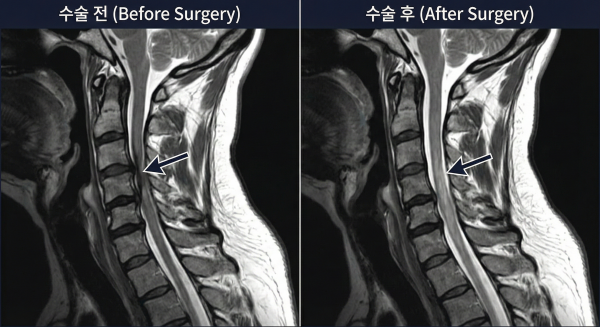

보존적 치료로 호전되지 않는 심한 협착층이나 디스크의 경우,

경추내시경감압술이 효과적인 대안이 됩니다.

이 치료법은 약 1cm 미만의 최소 절개를 통해 내시경으로 병변 부위만 정밀하게 제거합니다.